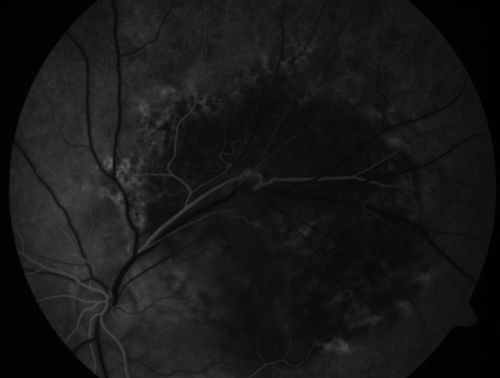

Retinal Pigment Epithelial Dysgenesis